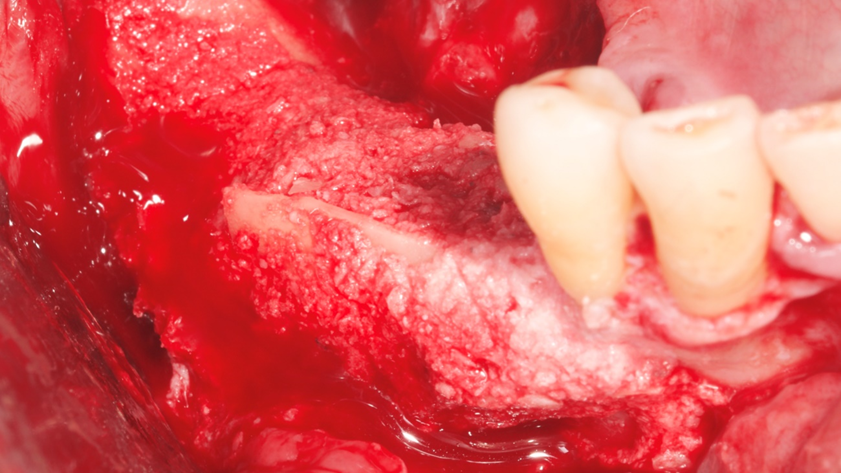

Homem de 60 anos foi encaminhado para reabilitação implantossuportada na região molar inferior direita (Figura 1). O volume ósseo remanescente tridimensional foi acessado por meio de tomografia computadorizada. Revelou uma deficiência vertical de modo que um aumento vertical foi planejado antes da colocação do implante. Seu histórico médico foi verificado e não foram encontradas comorbidades nem condições alérgicas. Não houve achados clínicos intraorais anormais, mas uma deficiência vertical na área molar inferior direita. Nenhum achado anormal foi perceptível no exame extraoral. Um enxerto autógeno em bloco ósseo dividido foi planejado para aumento horizontal e o ramo ipsilateral foi o local doador de escolha. A cirurgia foi realizada sob anestesia local com Articaína 4% e adrenalina 1:100.000. O paciente foi prescrito para enxaguar com Clorexidina 0,12% no pré-operatório, bem como tomar 1mg de Amoxicilina e 8mg de Dexametasona P.O. uma hora antes da cirurgia. Uma incisão mucoperiosteal foi realizada com bisturi número 15C desde o ramo mandibular até a borda mesiovestibular do primeiro pré-molar juntamente com uma incisão perpendicular obliquamente no vestíbulo mandibular. Após o descolamento da mucosa vestibular e liberação do nervo mentoniano, a mucosa lingual também foi descolada (Figura 2). Duas osteotomias verticais e uma horizontal foram realizadas no ramo mandibular com broca 701 para retirada do bloco ósseo necessário à reconstrução horizontal (Figura 3). Após a retirada do enxerto com auxílio de um elevador radicular, o bloco foi cortado longitudinalmente em dois pedaços finos com brocas discais e o osso esponjoso foi raspado para que pudesse ser utilizado como osso lascado (Figuras 4 a 8). Os blocos foram fixados na área edêntula. Um bloco foi fixado na face vestibular e o outro na face lingual. Cada um deles foi fixado com dois parafusos de osteossíntese de 1,5 mm e o osso lascado foi inserido no espaço entre eles (Figuras 9 e 10). A ferida foi fechada com fio de polipropileno 5-0, que foi retirado após 15 dias (Figura 11). A cirurgia cicatrizou sem intercorrências e o paciente recebeu prescrição de amoxicilina 500 mg P.O. a cada oito horas durante sete dias e ibuprofeno 600 mg a cada seis horas durante cinco dias.